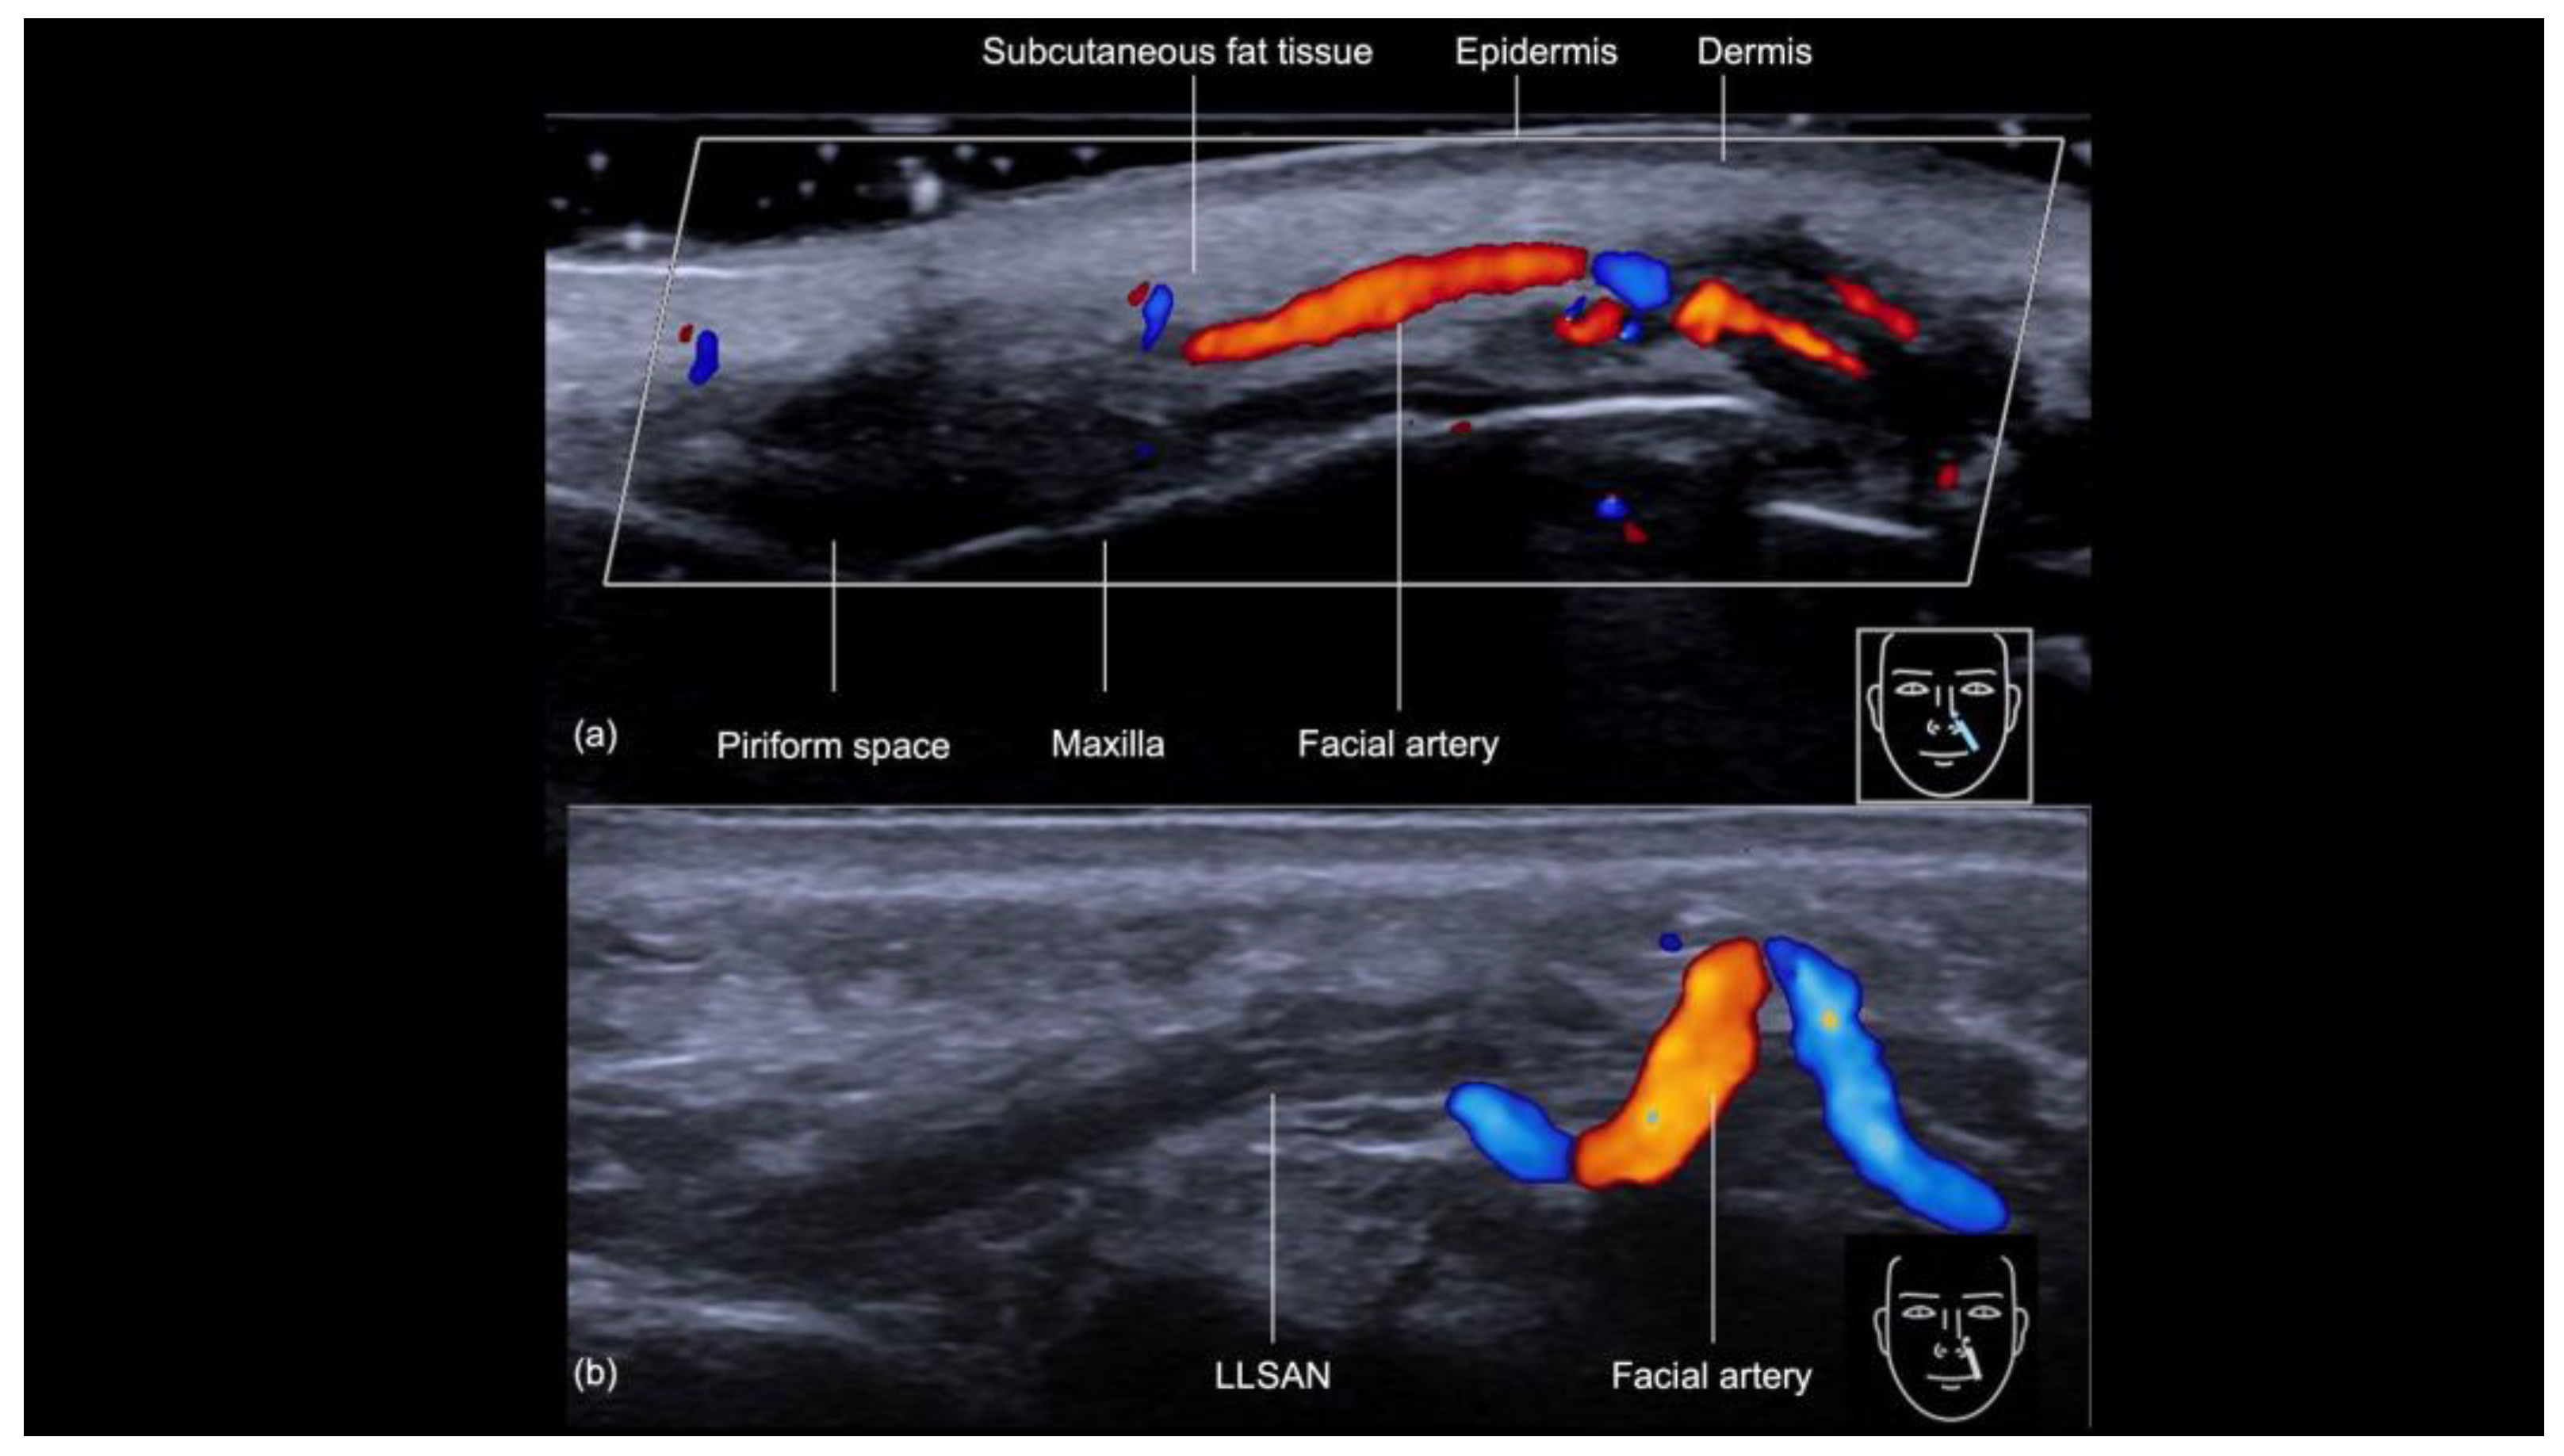

3.3.1. Sonographic Anatomy of the Nasolabial Fold

- Technique 1: Subcutaneous filler placement with a blunt cannula

- Technique 2: Supraperiosteal filler placement with a needle